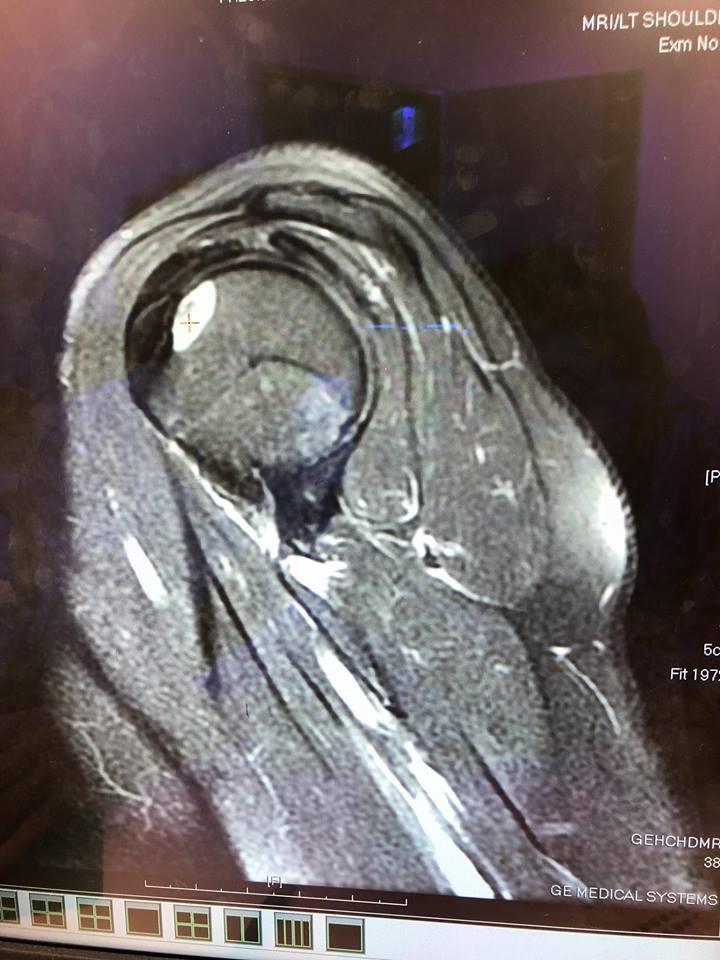

張語昕昨(5)日在臉書投下震撼彈,說明自己罹患了骨癌:「骨頭有洞」。她貼上肩膀骨頭核磁共振的結果,並說明醫生已經確認是良性腫瘤,表示目前不用開刀,不過仍需追蹤半年,樂觀的她也打上:「阿昕謝謝老天爺,讓我暫時不用開刀,還是可以拍照」生病仍不忘工作,相當敬業。她也寫道:「大家別忘了我是漢子阿昕‼️‼️‼️抗癌戰士,我正在抗癌,我覺得我有慢慢的進步,希望哪天我的腫瘤可以縮小一些,加油」堅強鼓舞自己和粉絲!